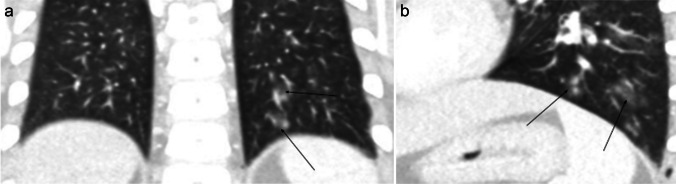

Affected patients with complicated pulmonary infection present with prolonged fever, respiratory symptoms, chest pain, and chest distress [40]. The most common findings on CT include lung abscesses, found in up to one-third of cases, and consolidations complicated by lung necrosis (Fig. 3). Pleural effusions are common, seen in up to two-thirds of cases. Pleural fluid is usually complex (loculated pleural fluid, with or without septations or split pleura sign), indicative of empyema. Hilar lymphadenopathy is occasionally seen [43]. Although rare, infection with the S. anginosus group should be considered in the differential diagnosis of pediatric patients presenting with empyema or lung abscess, regardless of their immune status.

Fig. 3.

Axial non-contrast-enhanced computed tomography images in a 14-year-old boy with Streptococcus anginosus infection who presented with fever, cough, and right-sided chest pain. a Lung window image shows a round lesion with a thick wall, surrounding ground-glass opacities and an internal air-fluid level consistent with a lung abscess (arrow). b Mediastinal window image better demonstrates the air-fluid level within the lung abscess (arrow)

Chest radiography and CT can be helpful in reaching the diagnosis. Typical chest radiographic findings are pleural effusion, hilar lymphadenopathy, and patchy pulmonary consolidations with ground-glass opacities. On CT, ill-defined pulmonary nodules and consolidation with round low-attenuation cystic lesions filled with fluid or gas can be seen (Fig. 7); intra-cystic worms may be detected [60–62]. When children from endemic areas present with respiratory symptoms, laboratory findings of eosinophilia, and imaging demonstrations pleural effusion and lung consolidations with internal cystic lesions, diagnosis of paragonimiasis should be strongly considered.

Fig. 7.

Axial non-contrast-enhanced lung window computed tomography images in a 7-year-old girl with paragonimiasis who presented to hospital with abdominal pain and subcutaneous nodules. a Image at the level of the mid lung zone shows ill-defined lung nodules (white arrows) and a left-sided pleural effusion (black arrow). b Image at the level of the lower lung zone shows ill-defined lung nodules (thin arrow) and alveolar opacification (thick arrow) (figure from “A retrospective clinical analysis of pediatric paragonimiasis in a Chinese children’s hospital from 2011 to 2019” by Qian et al.; licensed under CC BY 4.0; original cropped and annotated)